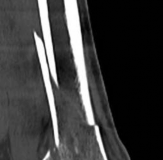

Temporary ankle-spanning external fixation was used to stabilize the fracture and soft tissues. X-rays taken after external fixation showed improved alignment and allowed for better understanding of the fracture pattern (Fig 2.2-2). Computed tomographic (CT) scanning with 3D reconstruction was performed for precise assessment of the fracture pattern of the tibial plafond. The CT revealed displaced fragments with a resultant intraarticular step-off and gap. The distal tibial metaphyseal fracture was multifragmentary. In addition, an associated long oblique fibular fracture was present (Fig 2.2-3).

Fig 2.2-3a–h A CT scan with 3D reconstruction.

a–d Sagittal (a–b), coronal (c), and axial (d) images demonstrate displaced posterior, anterolateral, and medial fracture fragments resulting in intraarticular step and gap. The incongruent tibiotalar joint is best appreciated on the sagittal scan.

e–h The 3D reconstructed images show the external fracture anatomy and general alignment.